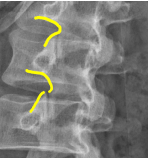

A: Hadley's S Curve

assesses for subluxation by looking for a smooth, continuous curvilinear line. No average or range is specified.